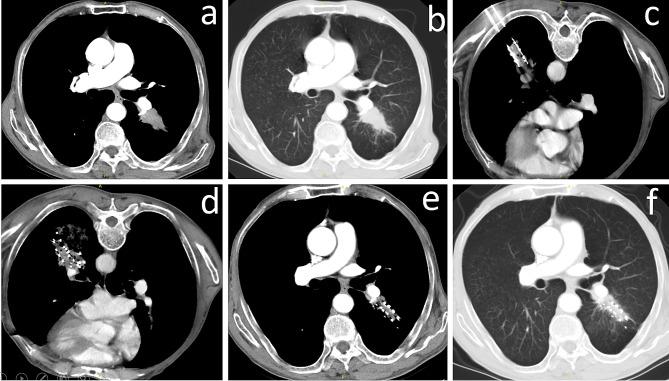

Patients with early-stage (T1-T2aN0M0) NSCLC who underwent CT-guided SABT or MWA between October 2014 and March 2017 at four medical centers were retrospectively analyzed. Survival, treatment response, and procedure-related complications were assessed.

A total of 83 patients were included in this study. The median follow-up time was 55.2 months (range 7.2-76.8 months). The 1-, 3-, and 5-year overall survival (OS) rates were 96.4%, 82.3%, and 68.4% for the SABT group (n = 28), and 96.4%, 79.7%, and 63.2% for MWA group (n = 55), respectively. The 1-, 3-, and 5-year disease-free survival (DFS) rates were 92.9%, 74.6%, and 54.1% for SABT, and 92.7%, 70.5%, and 50.5% for MWA, respectively. There were no significant differences between SABT and MWA in terms of OS (p = 0.631) or DFS (p = 0.836). The recurrence rate was also similar between the two groups (p = 0.809). No procedure-related deaths occurred. Pneumothorax was the most common adverse event in the two groups, with no significant difference. No radiation pneumonia was found in the SABT group.